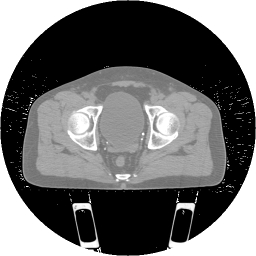

Abdominal CT scan is processed via our meshing pipeline. The focus of study in this image is the bladder and its volume occupancy and absorption of radiation, when in line with radiation beams to the prostate. (a): a slice of the original CT scan is shown. (b): same slice after our filtering step. (c): result of classification of the anatomic subregions, automatically segmented and colored differently (cross-section slice). (d): volume rendering of the abdominal region of the classified 3D image of the bladder, again shown in blue. (e): the bladder meshed using our hex mesher. Note the non-smoothness which leads to poor quality quadrilateral elements. (f): same mesh after quality improvement using geometric flow techniques. (g): the adaptive triangle mesh of the bladder. The hook (red) has been artificially chosen to require finer mesh adaptivity. (h): the same mesh as (g) after coarsening. Note the adaptive mesh density after coarsening.